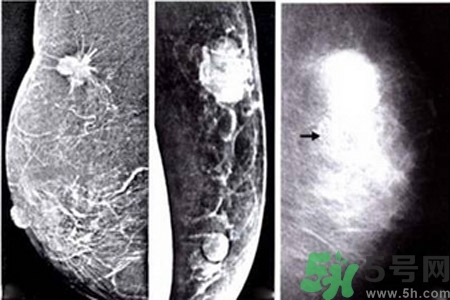

乳腺鈣化與腫塊的關(guān)系

鈣化可與腫塊并存,也可獨(dú)立存在;既可發(fā)生在病變內(nèi),也可獨(dú)立于腫塊之外。90%的導(dǎo)管原位癌是通過X線鉬靶照片發(fā)現(xiàn)的,且僅以乳腺內(nèi)鈣化作為惟一的表現(xiàn)形式。這是由于原位癌中央發(fā)生不規(guī)則壞死引起的鈣鹽在導(dǎo)管內(nèi)沉積或腫瘤細(xì)胞分泌而呈形態(tài)各異的的表現(xiàn)。

乳腺癌近幾年的發(fā)病率居高不下,女性朋友特別到了25歲之后,每年都要定期檢查乳房,已便及早發(fā)現(xiàn)疾病,盡快治療。醫(yī)院常用檢測(cè)乳腺癌的方法是采用乳腺鉬靶檢查,而診斷為乳腺鈣化的情況在這種檢查中顯示率也相當(dāng)?shù)母摺?/p>

乳腺鈣化是指可以在乳房造影看到鈣沉淀物,有多種因素可導(dǎo)致乳腺鈣化,如組織退變、壞死鈣鹽沉積,某些腫瘤分泌含鈣鹽的物質(zhì),使血管周圍組織鈣化。分析鈣化的形態(tài)、數(shù)目、部位以及與周圍結(jié)構(gòu)的關(guān)系,對(duì)辨別病變的性質(zhì)有較大的幫助。